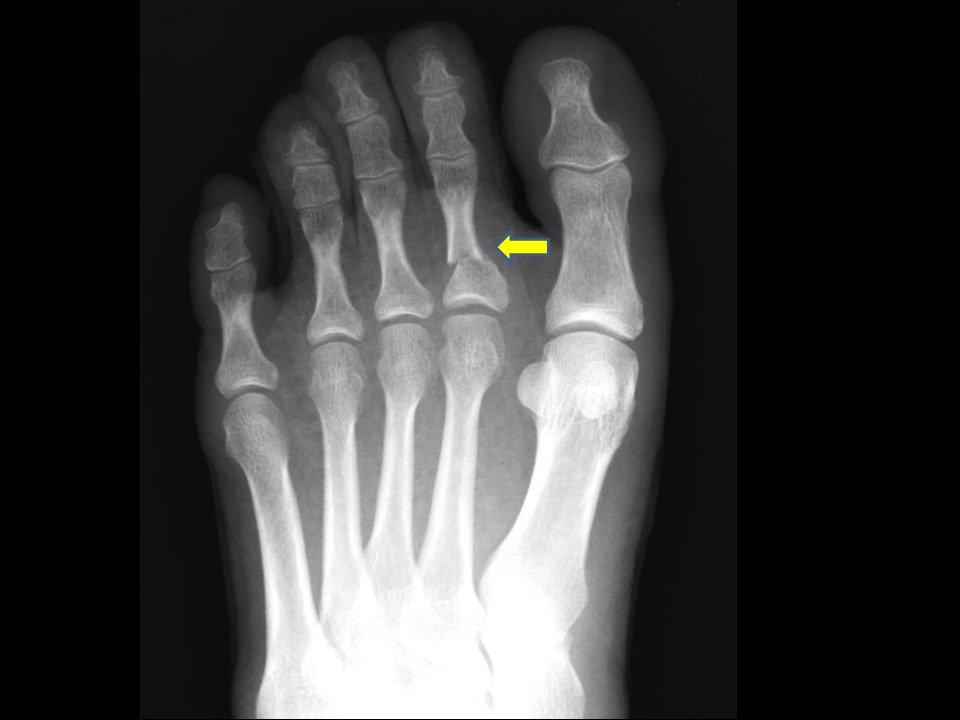

진단 방법과 X-ray 검사

의사는 통증 부위와 발가락 변형을 육안으로 확인한 뒤, X-ray로 골절선의 위치와 전위(뼈의 어긋남) 여부를 판별합니다. 단순 골절인지, 관절면을 침범한 복합 골절인지에 따라 치료 방향이 달라집니다. 경우에 따라 CT 촬영이 필요할 수도 있습니다. 엄지발가락처럼 체중이 집중되는 부위일수록 정확한 영상 진단이 중요합니다.